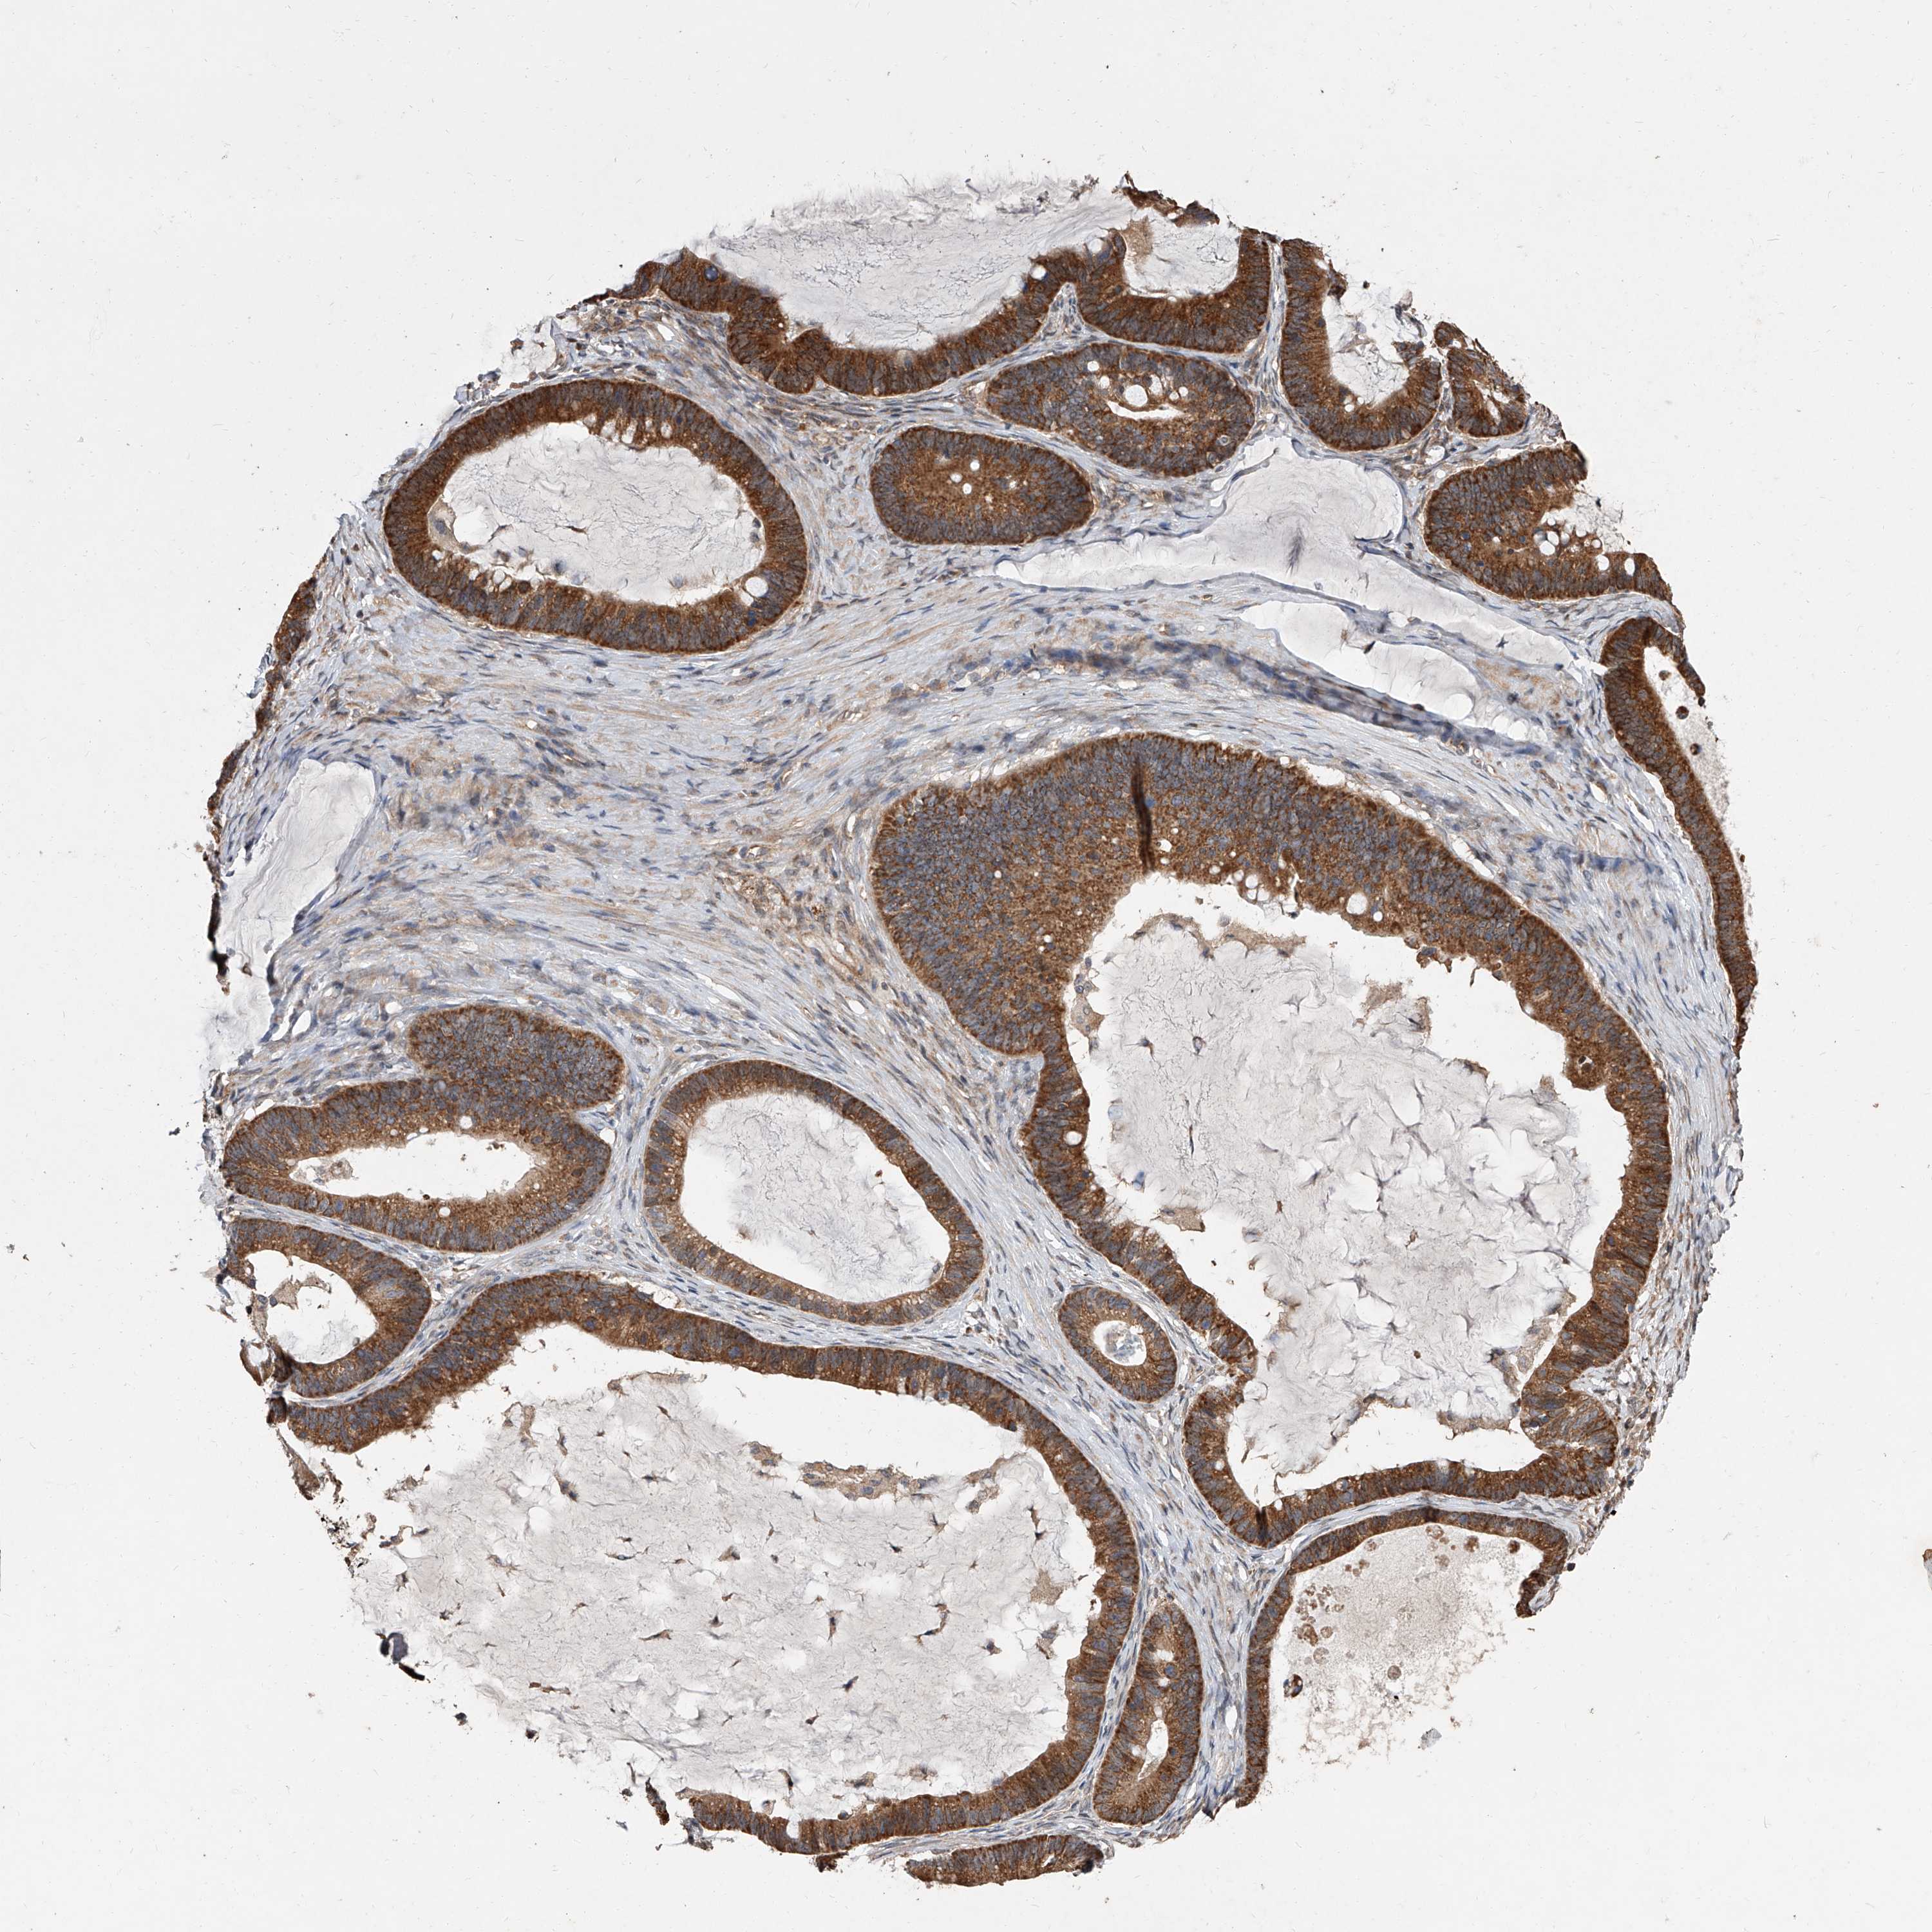

OVARIAN CANCER - Protein expressioni

A mouse-over function shows sample information and annotation data. Click on an image to view it in a full screen mode. Samples can be filtered based on level of antibody staining by selecting one or several of the following categories: high, medium, low and not detected. The assay and annotation is described here.

Note that samples used for immunohistochemistry by the Human Protein Atlas do not correspond to samples in the TCGA dataset.

Antibody stainingi

Antibody staining in the annotated cell types in the current human tissue is reported as not detected, low, medium, or high, based on conventional immunohistochemistry profiling in selected tissues. This score is based on the combination of the staining intensity and fraction of stained cells.

Each image is clickable and will lead to virtual microscopy that enables deeper exploration of all samples and also displays staining intensity scores, fraction scores and subcellular localization as well as patient and tissue information for each sample.

Antibody HPA030159

Antibody HPA030160

Antibody HPA030161

Cystadenocarcinoma, serous, NOS

Carcinoma, endometroid

Cystadenocarcinoma, mucinous, NOS

Carcinoma, NOS